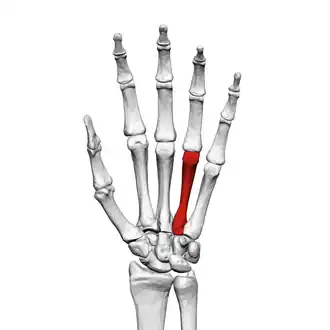

![]() Fourth metacarpal of the left hand (shown in red). Palmar view. | |

The fourth metacarpal bone (metacarpal bone of the ring finger) is shorter and smaller than the third.

The base is small and quadrilateral; its superior surface presents two facets, a large one medially for articulation with the hamate, and a small one laterally for the capitate.

On the radial side are two oval facets, for articulation with the third metacarpal; and on the ulnar side a single concave facet, for the fifth metacarpal.